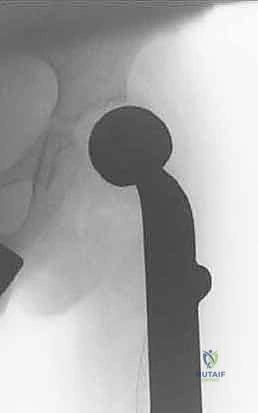

الطرف الاصطناعي القابل للتمدد (Expandable Endoprosthesis) هو معجزة هندسية طبية. يتكون من سبائك معدنية فائقة القوة والتوافق الحيوي (مثل التيتانيوم والكوبالت كروم). يتم زراعته داخل الجسم ليحل محل العظم المفقود والمفصل (مثل مفصل الركبة الصناعي).